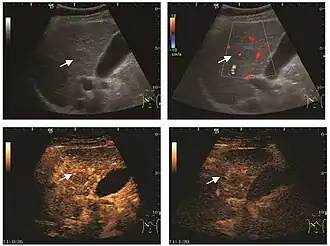

Liver abscess (2D and CEUS). 2D Examination reveals the fluid nature of the mass and imprecise delineation. CEUS examination shows congestion in the surrounding liver parenchyma and excludes a vascular tumor.

Liver abscess have heteromorphic ultrasound appearance, the most typical being that of a mass with irregular shapes, fringed, with fluid or semifluid content, with or without air inside. Doppler examination shows the lack of vessels within the lesion. CEUS exploration shows hyperenhancement during arterial phase close to the lesion, this being suggestive of a liver parenchymal hyperemia. During venous and sinusoidal phase the pattern is hypoechoic, and the central fluid is contrast enhanced. CEUS examination is useful because it confirms the clinical suspicion of abscess. In addition, it allows for an accurate measurement of the collection size and an indication regarding its topography inside the liver (lobe, segment).